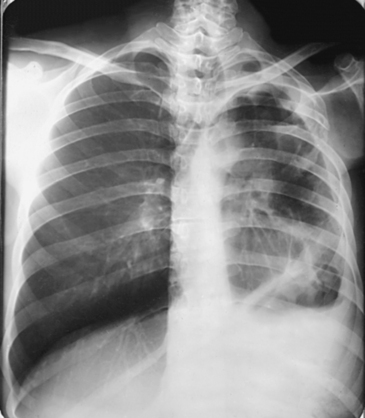

Structures shown: An AP projection of the thoracic viscera (Fig. 10-51) shows an image similar to the PA projection (Fig. 10-52). Being farther from the IR, the heart and great vessels are magnified and engorged, and the lung fields appear shorter because abdominal compression moves the diaphragm to a higher level. The clavicles are projected higher, and the ribs assume a more horizontal appearance.

For radiography of the heart and lungs, the patient is placed in an upright position whenever possible to prevent engorgement of the pulmonary vessels and to allow gravity to depress the diaphragm. Of equal importance, the upright position shows air and fluid levels. In the recumbent position, gravitational force causes the abdominal viscera and diaphragm to move superiorly; it compresses the thoracic viscera, which prevents full expansion of the lungs. Although the difference in diaphragm movement is not great in hyposthenic individuals, it is marked in hypersthenic individuals. Figs. 10-10 and 10-11 illustrate the effect of body position in the same patient. The left lateral chest position (Fig. 10-12) is most commonly employed because it places the heart closer to the IR, resulting in a less magnified heart image. Left and right lateral chest images are compared in Figs. 10-12 and 10-13.